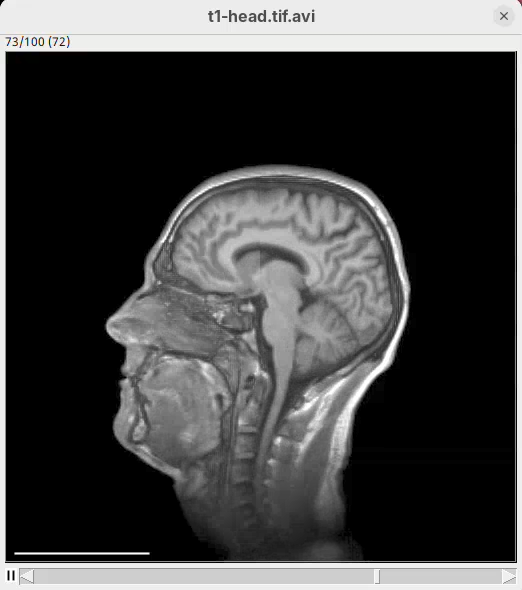

We will begin by visualizing an MRI dataset of a human head that is bundled in Fiji.

- Go to

File>Open Samples>T1 Head (16-bits).

From frame 0 to frame 9 rotate by 360 degrees horizontally- Press

Run.

A new window will show up with an image stack of 10 frames containing the generated animation.

- Press play or and watch the head turn 360 degrees during these 10 frames.

Note that we did not need to define how many degrees the head would turn for each frame. We can simply state that we need the head to turn 360 in these 10 frames and 3Dscript will deal with it.